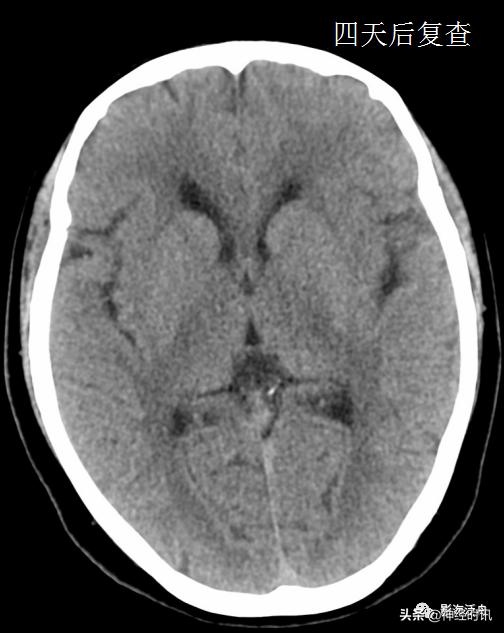

典型的大脑镰前部少量蛛血,血肿的边缘毛糙(红箭)且抵达胼胝体膝部的前缘(黄箭头)。4天后复查头颅CT平扫,相应部位少量蛛血基本吸收。